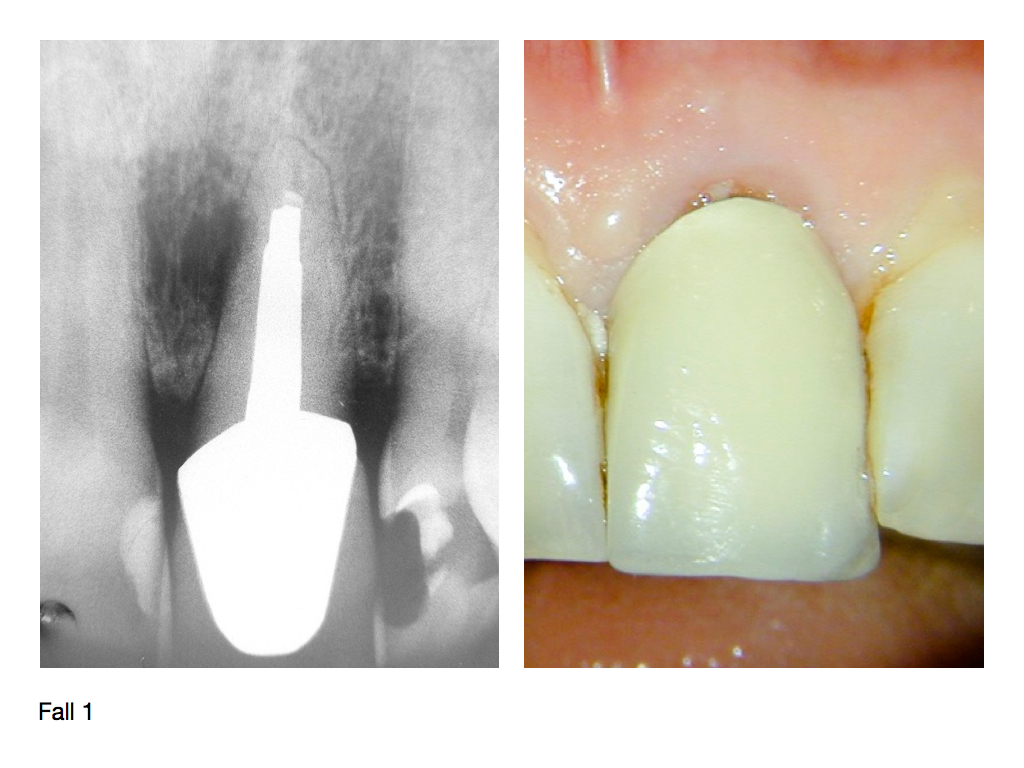

IF.003 Veröffentlicht 3. November 2012 am 1024 × 768 in Zahnerhalt „austherapierter“ Zähne durch endochirurgische Maßnahmen